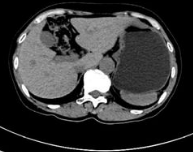

苏州看肝脏结节好的医生提醒:临床上很多患者在有肝结节时就会想到是不是也与肝癌有关系,实际上肝结节是一个非常广泛的定义,而肝癌它作为一个肿瘤,是一个结节性的病变。不过发现肝结节,并不一定就是肝癌,但是如果出现这种性质的结节,就需要做进一步的深入检查,确定是什么病变。 肝结节与... [详情]

苏州治疗肝结节好的医院提醒:肝结节有良性与恶性之分,但良性与恶性的区别,跟结节的形状没有直接关系。苏州国医堂名医工作室孙嗣章说不规则肝结节,有可能是恶性,当然有一部分不规则结节也是良性。 结节的形状只是判断良性或者恶性的指标之一,并不是不规则结节就是恶性。所以对于这种不规则... [详情]